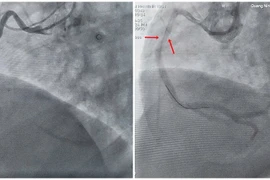

Bệnh nhân 77 tuổi ngưng tim sau nhồi máu cơ tim được cấp cứu kịp thời, hồi phục sau can thiệp mạch vành toàn diện tại Quảng Nam.